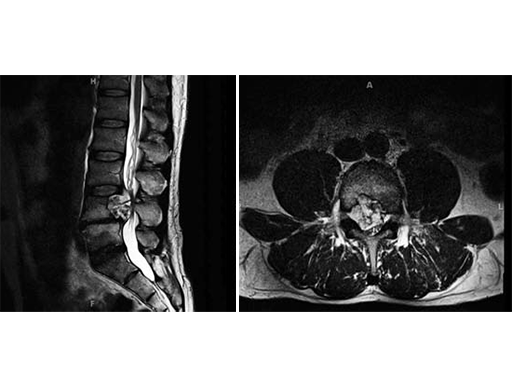

The patient was admitted for evaluation, and on MRI, was found to have a lesion at the L4 vertebral body, extending into the epidural space and compressing the cauda equine.

The patient was admitted for evaluation, and on MRI, was found to have a lesion at the L4 vertebral body, extending into the epidural space and compressing the cauda equine. The lesion was biopsied and found to be a chordoma, so he was transferred to the Neurosurgery department at Johns Hopkins Hospital for further management. His initial examination there was normal; motor strength 5/5 in all extremities, intact sensation, and reflexes present at 2+ throughout.